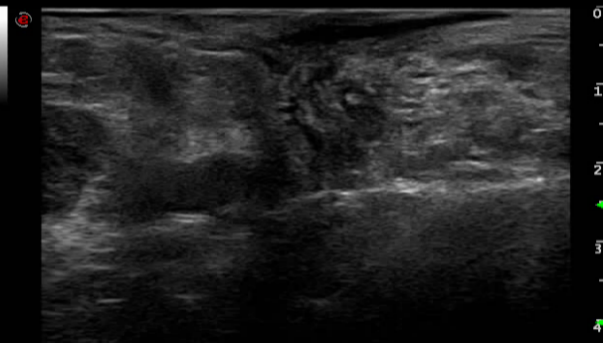

术前诊断

百胜彩超怎么样【州医先进设备】精准诊断引领精准治疗(十)——介入超声新利器,百胜MyLab 9引领精准医疗_https://www.jmylbn.com_新闻资讯_第7张

术后评估